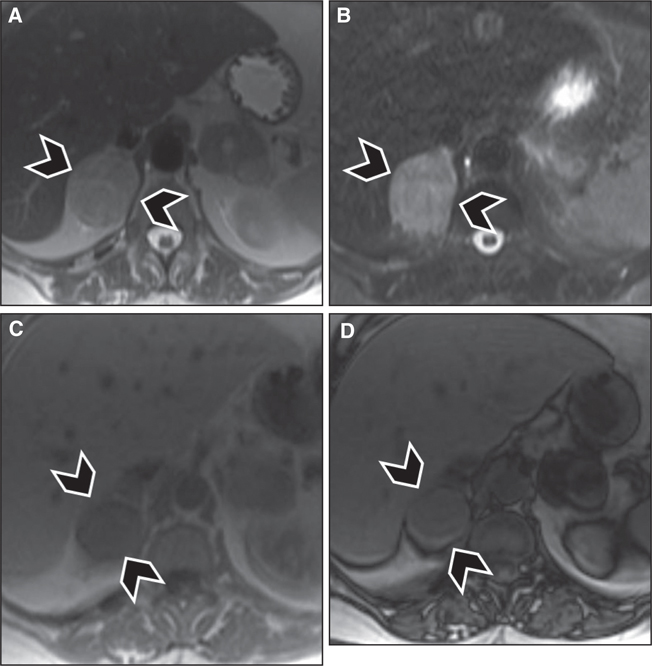

On MRI, like most tumors, pheochromocytomas demonstrate hypointense signal on T1 weighted images and hyperintense signal on T2 weighted images. This rather noncharacteristic appearance renders MR nonspecific for the diagnosis of pheochromocytoma, despite its high sensitivity. Classically, pheochromocytomas were described to have a very hyperintense signal on T2 weighted images, giving them a “light bulb” manifestation; this sign is distinctive in only 10% of lesions but might be helpful in two-thirdsd of pheochromocytomas (23). Another classical sign of paragangliomas, seen both on T1 and on T2 weighted images, is “salt-and-pepper” appearance, which is seen due to the presence of punctate areas of low-signal intensity corresponding to flow voids from tumor vascularity, and hyperintense signal corresponding to areas of hemorrhage in the tumor. This sign has been described more with head and neck paragnagliomas than with trunk paragnagliomas, and is also neither sensitive nor specific, as it can be seen with any hypervascular tumor, namely, in angiofibromas (19). Chemical shift imaging can diagnose intralesional microscopic fat such as that typically seen in adrenal adenomas, but it does not accurately differentiate adenomas from pheochromocytomas because the latter can contain intralesional fat from lipid degeneration (24, 25). Signal heterogeneity within the tumor due to hemorrhage, cystic transformation, and calcifications remains a helpful feature in differentiating pheochromocytomas from benign adenomas (Figure 5). Paragangliomas again demonstrate imaging features similar to pheochromocytomas. Enhancement characteristics on MRI are similar to CT, as PPGLs demonstrate rapid and avid enhancement, but up to one-third of pheochromocytomas have overlapping washout characteristics with adrenal adenomas (20, 21).

Fig 5

Figure 5 Right adrenal pheochromocytoma (arrowheads) in a 72-year-old female patient. Nonspecific signal intensity characteristics are seen, with intermediate to hyperintense signal seen on (A) T2-weighted images and (B) fat-suppressed T2-weighted images (turbo Inversion Recovery sequence), and hypointense signal seen on (C) in-phase T1-weighted images, and no signal loss on (D) out-of-phase images to suggest intralesional microscopic fat.